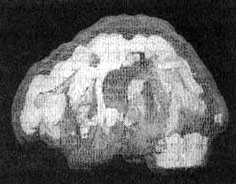

Мозг Линды. Результаты сканирования SPECT

Трехмерное изображение — активный мозг, вид сбоку.

До лечения: обратите внимание на выраженное усиление активности в поясной системе, в базальных ганглиях и в лимбической системе.

После лечение зверобоем. Активность в поясной системе, в базальных ганглиях и в лимбической системе нормализовалась.